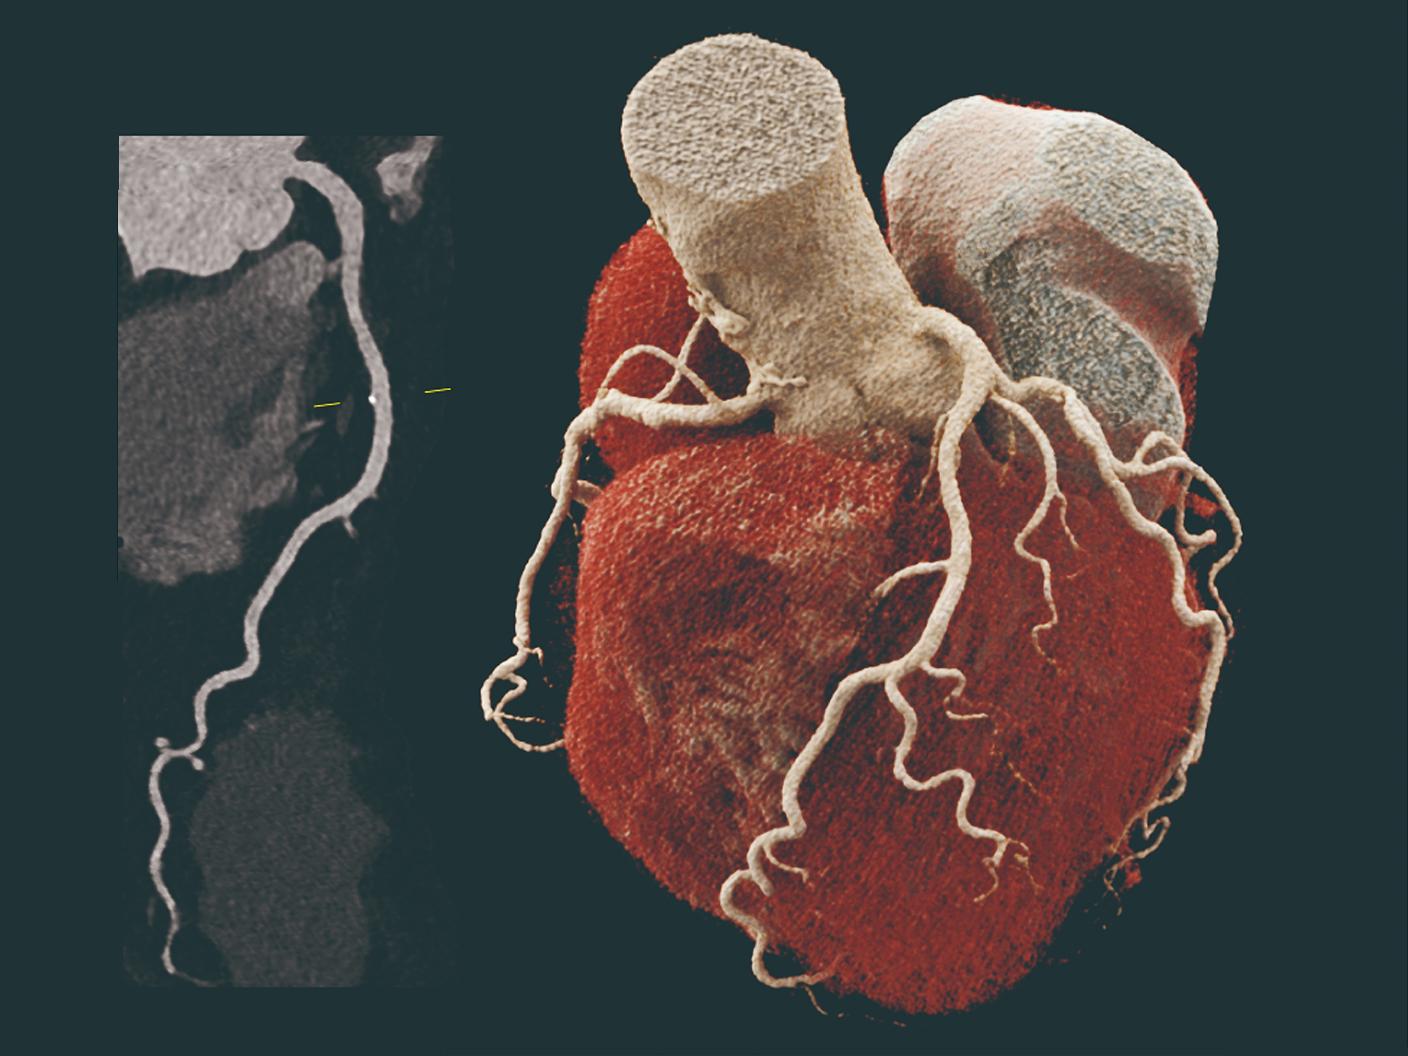

「NAEOTOM Alpha.Pro」は、当社のデュアルソースCT技術とフォトンカウンティング技術を融合し、CT画像診断の可能性を広げることを目指しています。主に心血管向けの検査ニーズに応えるべく、高い時間分解能と最大491mm/秒の高速スキャンにより、心拍の影響を受けにくい精度の高い心血管イメージングを可能にします。また、心血管の撮影のみならず、呼吸器科での検査においては患者さんの息止め時間を短縮したり、小児科において鎮静剤を必要としない検査の可能性を広げるなど、患者さんの負荷軽減に向け幅広い診療科で使用いただけます。

「NAEOTOM Alpha.Peak」および「NAEOTOM Alpha.Pro」が持つ高い時間分解能は、血管系の描出、動脈瘤の詳細な解析、動脈解離の評価などにおいて高い評価をいただいているだけでなく、特に高度石灰化冠動脈を有する心疾患患者さんの診断・治療において、侵襲的なカテーテル検査に代わるものとして、患者さんの身体的負荷軽減や、診断から治療までに要する時間の軽減への貢献が期待されています*4 。